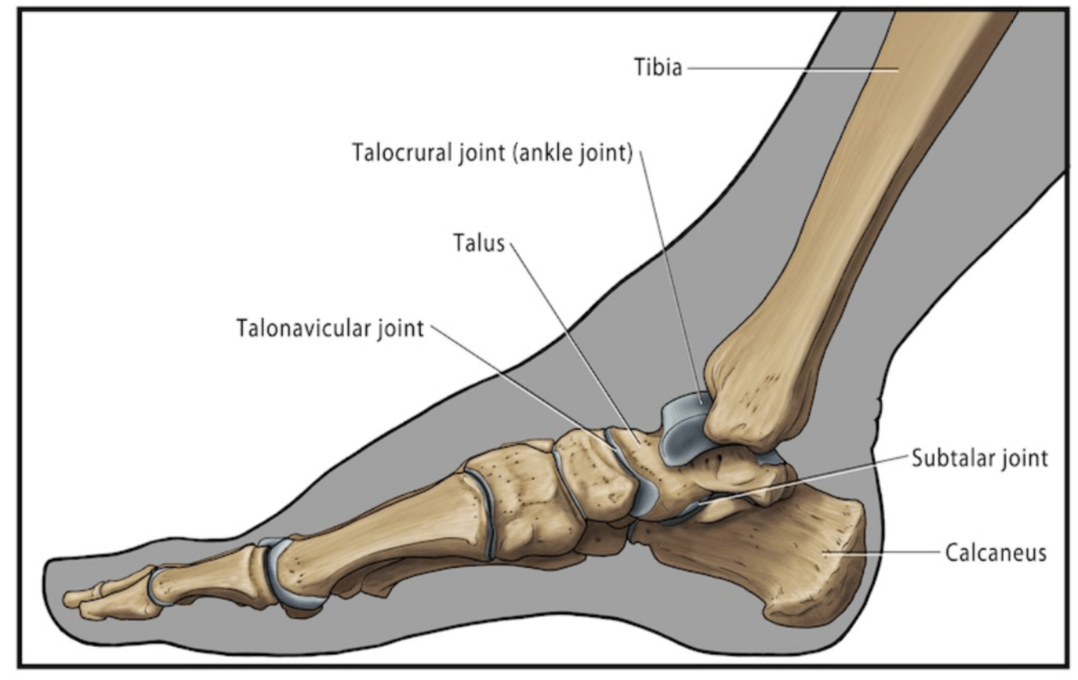

Name the hinge joint that's main motion is plantar flexion and dorsiflexion of the foot.

What is Talocrural (Tibiotalar) Joint?

-A hinge joint located between the talus and the medial malleolus, and the lateral malleolus

- Due to the configuration of the talus and the ankle mortise, the ankle is more stable in dorsiflexion than plantar flexion. This is the reason why 80% of ankle sprains occur in plantar flexion.

Name a joint that acts mostly as a shock absorber, and also allows internal/external rotation of the leg while the foot is fixed

What is Subtalar (Talocalcaneal) Joint?